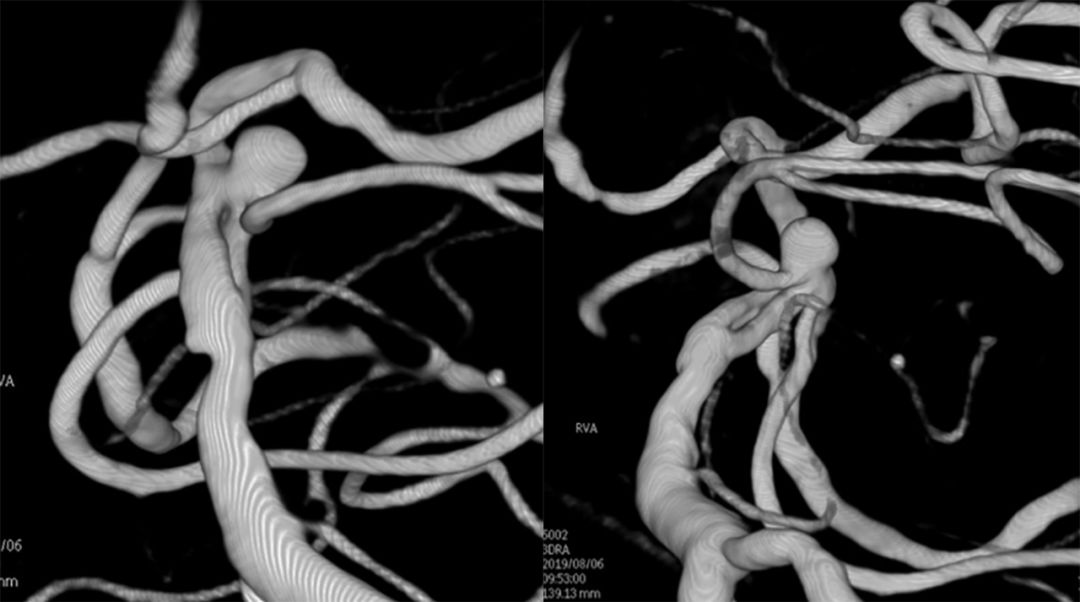

全脑血管造影(本院,2019-8-1 ):基底动脉顶端夹层或者开窗,左侧小脑上动脉瘤(图4)。

图4

基底动脉进行三维血管重建:基底动脉有较粗和较细的2个管腔,左侧小脑上动脉瘤大小约2.3*2.1 mm(图9)。

图9

进行上述三次微量造影均可见双侧大脑后动脉显影,以及结合基底动脉三维重建图像,故判断基底动脉属于开窗,而非夹层。由于载瘤动脉较细,拟行单微管动脉瘤栓塞术。